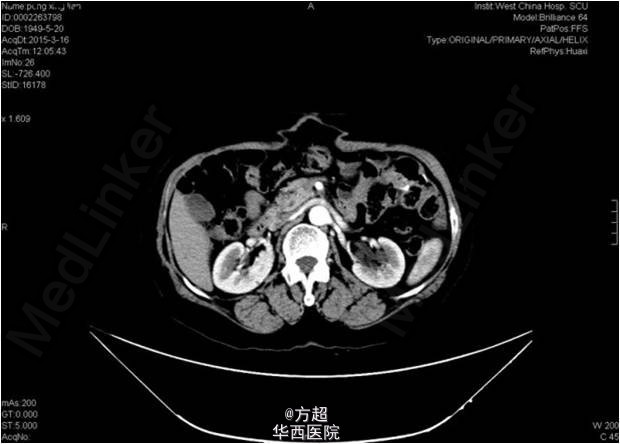

入院查体:肿瘤相关指标未见明显异常;腹壁原手术切口处活动性包块,大小12*11cm,质软,可触及肠管;腹部CT可见腹壁缺损,大小约8cm,腹腔脏器未见异常,未见直肠癌复发及转移征象。